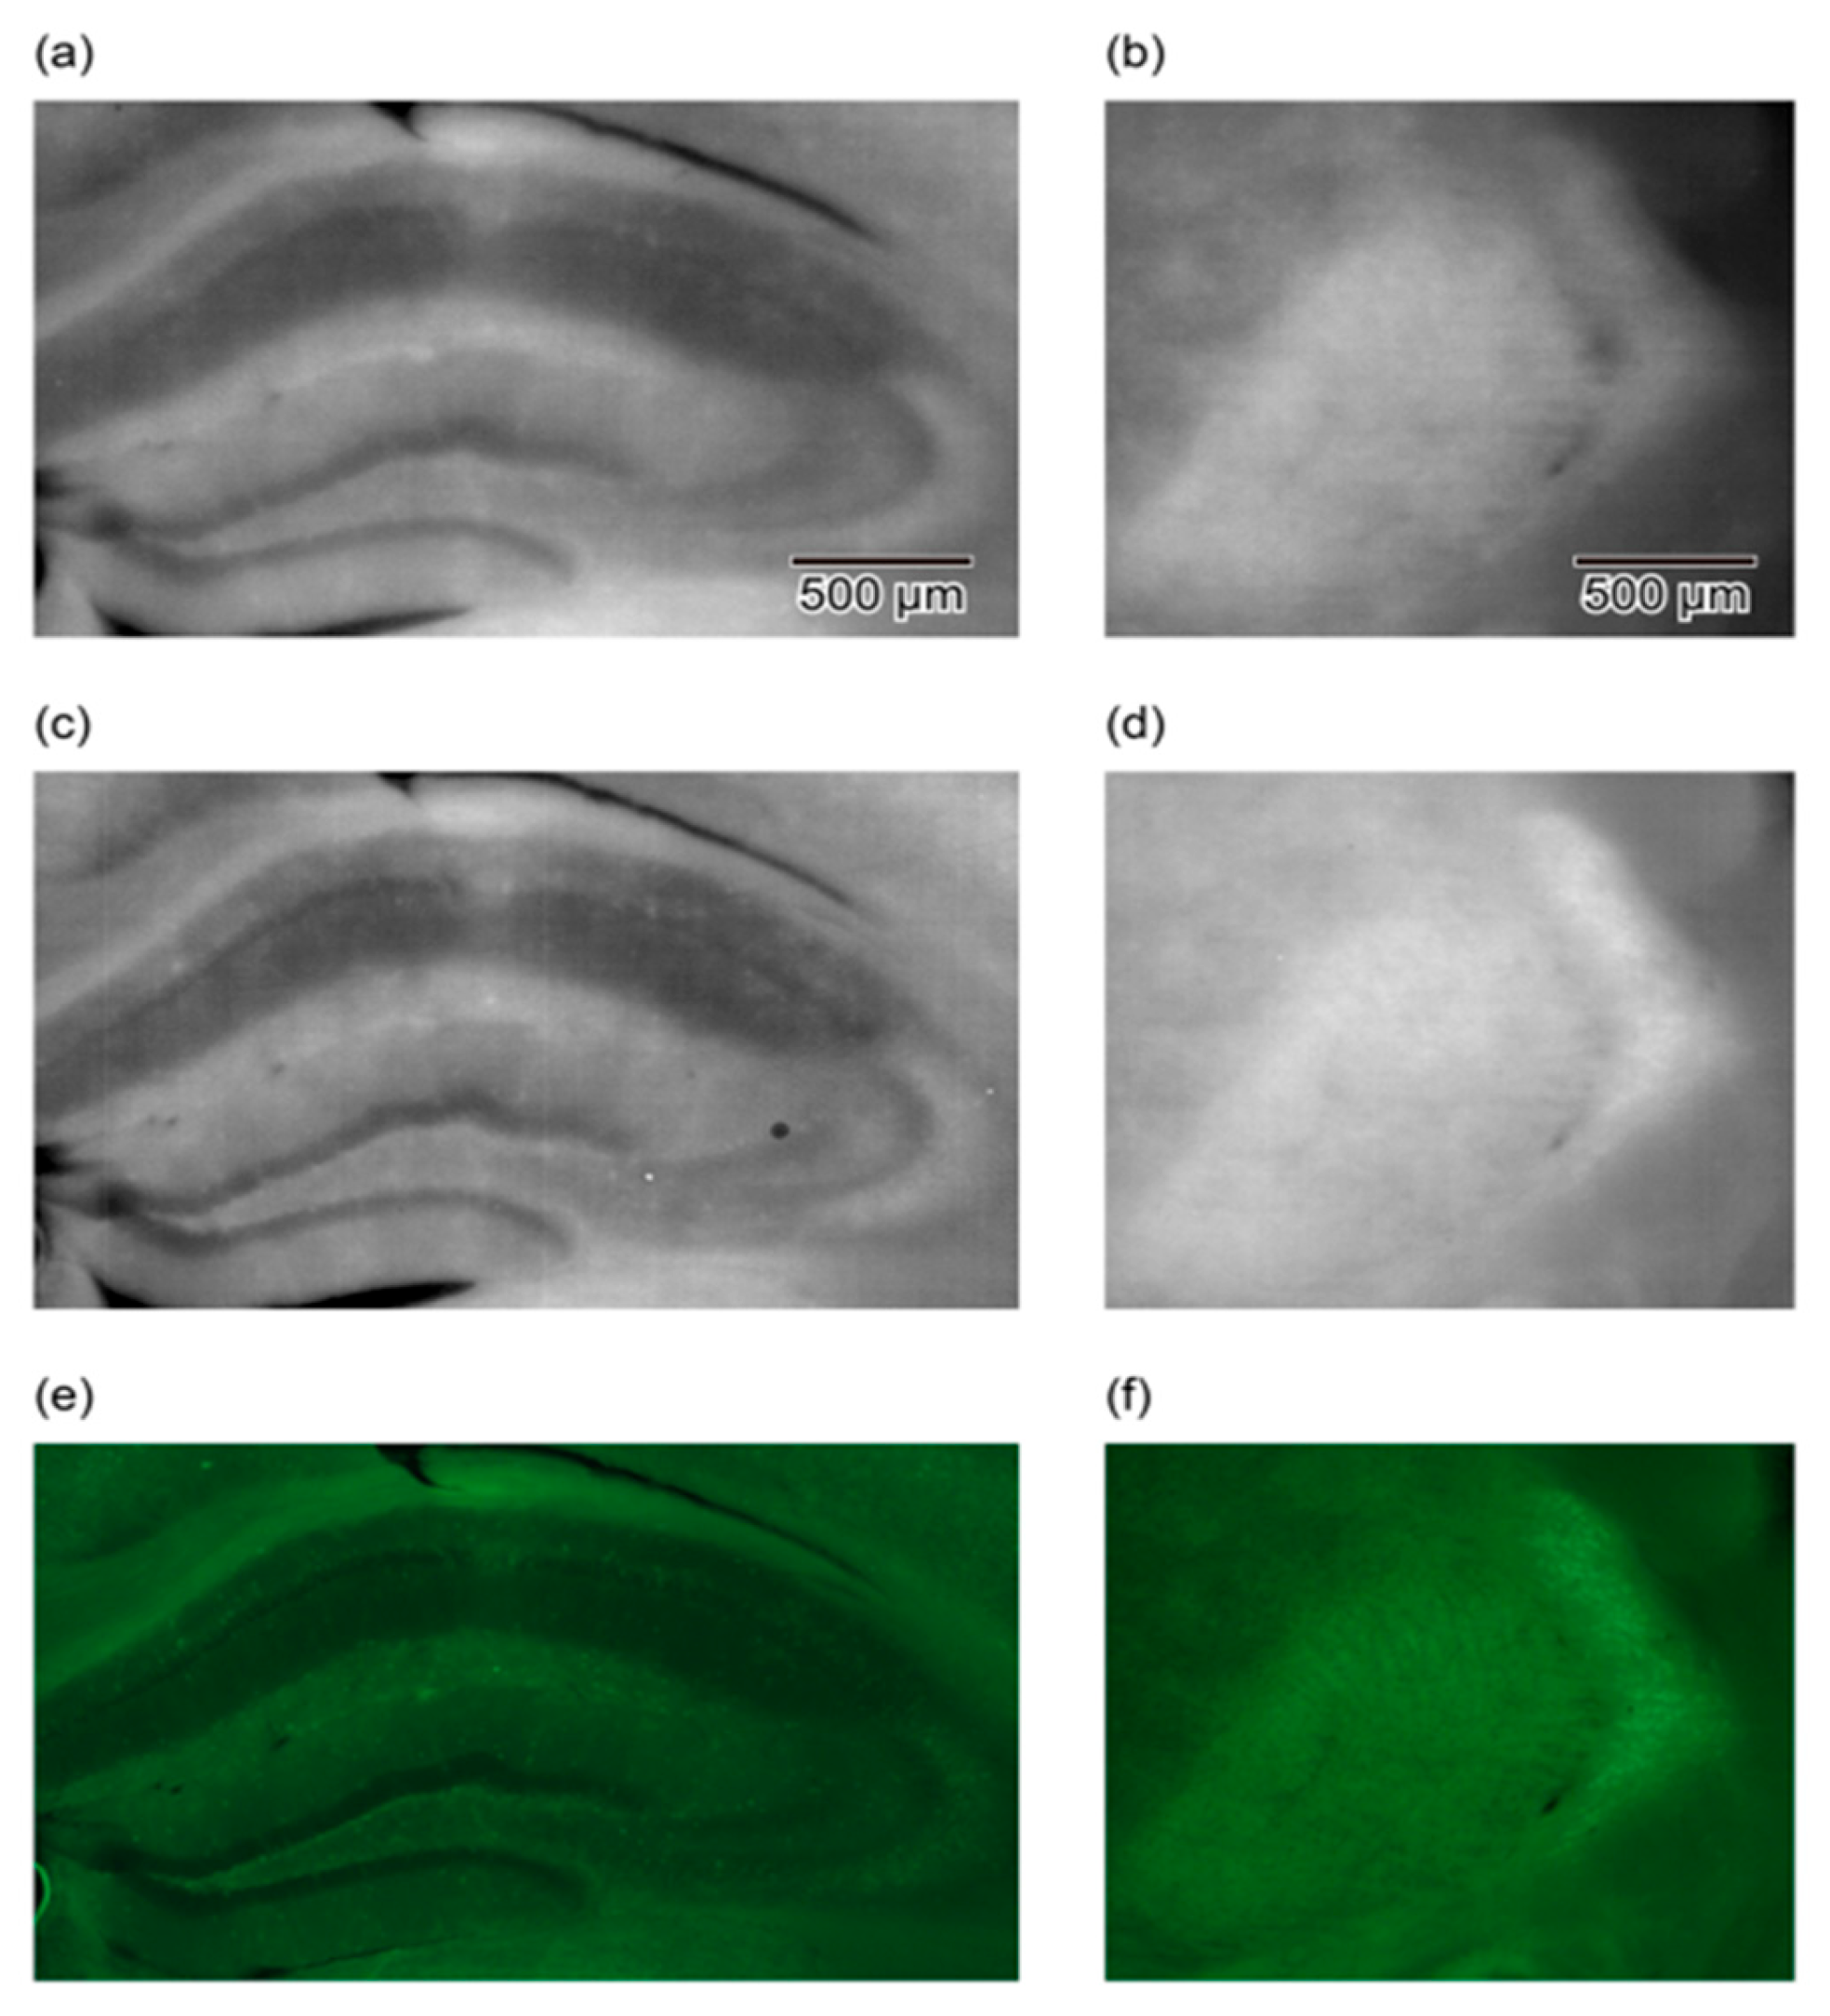

In other studies, conducted using LLFM, a 100 µm thick brain slice from a green fluorescent protein (GFP) transgenic mouse was imaged to detect the fluorescent cell bodies within the brain slice. The slice was then placed directly on the device and imaged, and almost the whole slice was observed in a single shot [47,48]. Figure 4 compares images obtained using three different imaging setups: a lensless device with a hybrid longpass filter, a lensless device with a hybrid bandpass filter, and a conventional lens-based fluorescence microscope. The images showcase the hippocampus and reticular thalamic nucleus regions of a GFP-labeled mouse brain slice. The comparison highlights that the contrast and quality of the bandpass filter images are comparable to those obtained with the traditional fluorescence microscope, demonstrating the efficacy of the hybrid bandpass filter in reducing the autofluorescence and enhancing the GFP signal detection. This improvement underscores the potential of the lensless device for detailed biological imaging applications, offering a portable and cost-effective alternative to conventional microscopy techniques.

Figure 4. Comparison of imaging results for hippocampus (a,c,e) and reticular thalamic nuclei (b,d,f) using LLFM and lens-based microscope. (a,b) Images obtained with a lensless imaging device featuring a hybrid longpass filter. This device includes a longpass interference filter to reflect the excitation light and an absorption filter to reject the scattered excitation light, enhancing the fluorescence detection. (c,d) Images of the same areas obtained with a lensless imaging device equipped with a hybrid bandpass filter. This improved filter setup incorporates both a shortpass interference filter and an absorption filter, effectively rejecting autofluorescence and scattered excitation light, resulting in clearer images with higher contrast and more detectable cell bodies. (e,f) Images captured with a conventional lens-based fluorescence microscope using a 5× objective lens with a numerical aperture (NA) of 0.1. These images serve as a benchmark to compare the performances of the lensless devices, showing similar levels of image clarity and contrast in detecting GFP-labeled cell bodies. The comparison demonstrates that the hybrid bandpass filter significantly enhances the performance of lensless fluorescence imaging, approaching the quality of conventional microscopy. Reproduced with permission from Ref. [49]. Copyright 2019, AIP Publishing.